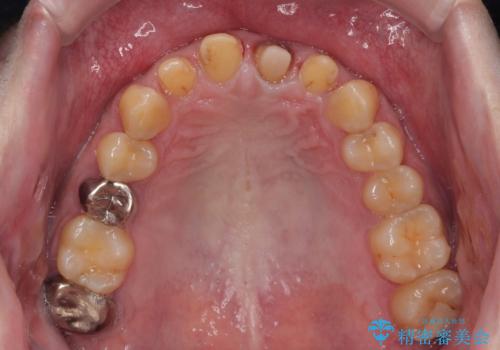

- 前歯の見た目を良くしたいとのことで来院された患者様です。今までに保険のプラスチック(コンポジットレジン)で虫歯の治療をしており経年的な劣化により着色が目立つようになっていました。また歯と歯の隣り合っているところに段差もあり虫歯になっていたり、詰め物も外れていたため前歯4本のオールセラミッククラウンによる治療を行うこととなりました。

拡大鏡視野下で保険のプラスチック(コンポジットレジン)、虫歯、左上1の被せものを除去し、オールセラミッククラウンに適した形にしました。